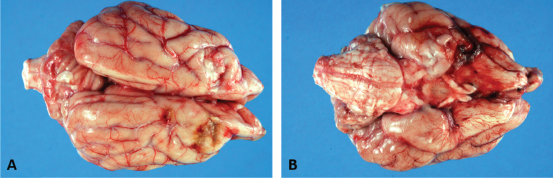

Fig. 3. Dorsal (A) and ventral (B) gross views of the brain showing focally extensive thrombosis of the right ventral cerebral artery resulting in an ischemic encephalopathy to the regions supplied by this artery and the loss of tissue which manifested as the depressed areas of malacia on the dorsal view.

Necropsy findings included granulomatous myositis with fibrosis overlying the ventral aspect of the right masseter muscle, extending into the buccal submucosa and concurrent moderate multifocal chronic granulomatous lymphadenitis of the maxillary lymph nodes. Two lesions consistent with encephalomalacia were identified in the cerebral cortex: the first, a 1.5 cm × 1 cm, irregular, focal tan-brown depressed soft area within the right rostral and dorsal cerebral cortex just caudal to the median raphe, and the second, a 1 cm × 1 cm area associated with the left rostral cerebral cortex (Fig. 3). Severe, multifocal malacia was present in both the dorsal right hippocampus and right caudate nucleus. A firm thrombus was present in the rostral right cerebral artery of the right cerebrum (Fig. 3). Finally, along the right ventral calvarium, presumptive chronic multifocal, focally extensive proliferative osteitis was identified with compression and replacement of portions of the right optic nerve and chiasm (Fig. 4). No other gross lesions consistent with L. giganteum infection were identified outside the CNS and soft tissues of the head in a complete necropsy.

Within the brain, there was subacute to chronic, multifocal to coalescing, severe, granulomatous, lymphoplasmacytic, and neutrophilic meningoencephalitis predominantly of the right telencephalon and diencephalon associated with arteritis and arterial thrombosis of the right cerebral artery. Moderate chronic multifocal encephalomalacia was present bilaterally within the rostral cerebrum (Fig. 6). Numerous intralesional hyphae were identified in all lesions. Culture yielded a hyphal organism with morphologic features consistent with an oomycete, and PCR sequencing was consistent with the previously obtained L. giganteum isolate from this dog.